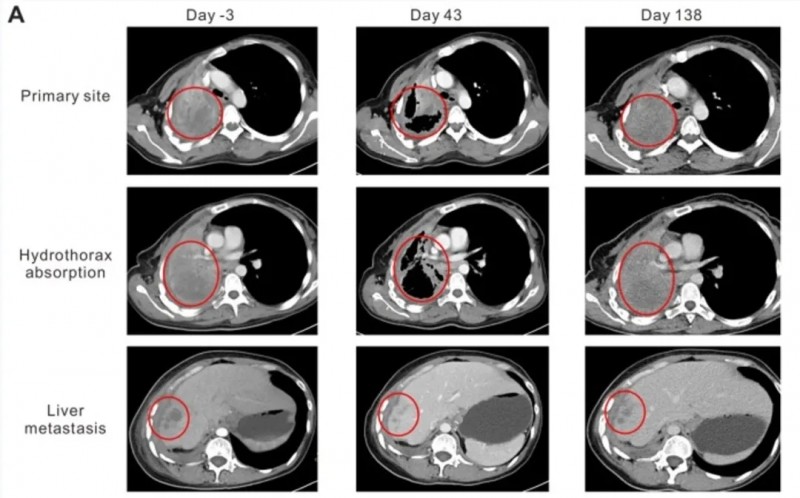

结果显示:首次输注后第43天,CT检查显示显著疗效,原发性肺部病灶从95×86×54mm缩小至64×44×54mm,肝转移灶从19.8×19.6×20mm缩小至10×10×10mm,胸腔积液完全吸收、肺成功复张(详见下图)。根据RECIST1.1标准,疗效评估为部分缓解(PR)。截至2017年10月10日,患者仍存活且病情稳定(SD),进一步印证了该疗法的长期获益潜力。

▲图源“Oncol Lett”,版权归原作者所有,如无意中侵犯了知识产权,请联系我们删除